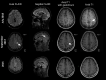

Multiple sclerosis (MS) is a common autoimmune disease of the central nervous system, causing neurological disability in young adults. A growing understanding of its immunopathogenesis has led to an expanding array of therapies. Notable new advances in disease-modifying therapies for relapsing forms of multiple sclerosis that are based on anti-inflammatory activity have recently been developed. Management of progressive MS is still challenging. Data published in 2014 suggested that daily high doses of biotin, a vitamin involved in myelin synthesis, might have a beneficial impact on disability and progression in progressive MS. However, some patients worsened while on biotin without any clear explanation for this effect. We report the case of a 41-year-old patient suffering from primary progressive (PP) MS who presented after 16 months of treatment with high doses of biotin (QIZENDAY) with worsening of his Expanding Disability Status Scale (EDSS) score and the appearance of a symptomatic new T2 pseudo-tumoural lesion on brain magnetic resonance imaging (MRI), suggestive of tardive inflammatory reactivation possibly due to the biotin. The newer and more effective therapies for MS are, however, associated with risks that necessitate an active management strategy and continuous vigilance. Physicians should be aware of iatrogenic neurological complications and the possible paradoxical effects of biotin. Future treatment approaches to progressive MS must include identification of a biomarker of disease activity. The study of neurofilaments in the cerebrospinal fluid (CSF) and the serum could be of interest when determining the optimal treatment strategy.